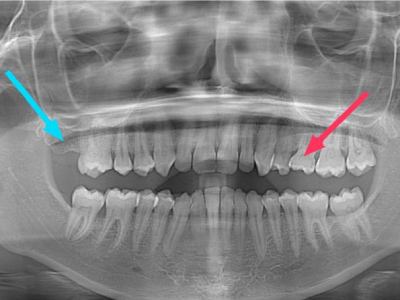

El diagnóstico de la agenesia dental se realiza mediante un examen clínico y radiográfico. El dentista realizará una evaluación completa de la boca del paciente y solicitará radiografías dentales, como radiografías intraorales, panorámicas o tomografías computarizadas.

La agenesia dental puede afectar a cualquier diente, pero algunos son más propensos a verse afectados. Los terceros molares (muelas del juicio) y los segundos premolares son los dientes más comúnmente afectados por la agenesia dental. Los incisivos laterales superiores (los dientes situados al lado de los dos incisivos centrales superiores) también son propensos a la agenesia dental, y su ausencia puede tener un impacto estético significativo.

Es importante distinguir la agenesia dental de los dientes retenidos o incluidos. Mientras que la agenesia dental implica la falta de desarrollo de un diente, los dientes retenidos o incluidos se refieren a dientes que no han erupcionado adecuadamente en la boca y quedan atrapados dentro del hueso. Es común en las muelas del juico o terceros molares y con menor frecuencia en los caninos superiores.